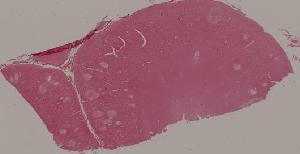

88. Chronic cavitary tuberculosis of the lung

89. Tuberculous lymphadenitis

90. Lepromatous leprosy of the skin

91. Tuberculoid leprosy

92. Typhoid fever of intestine

95. Poliomyelitis

96. Pulmonary aspergillosis

97. Amebic colitis

98. Schistosomiasis of the colon

99. Experimental acute schistosomiasis of the liver (rabbit)